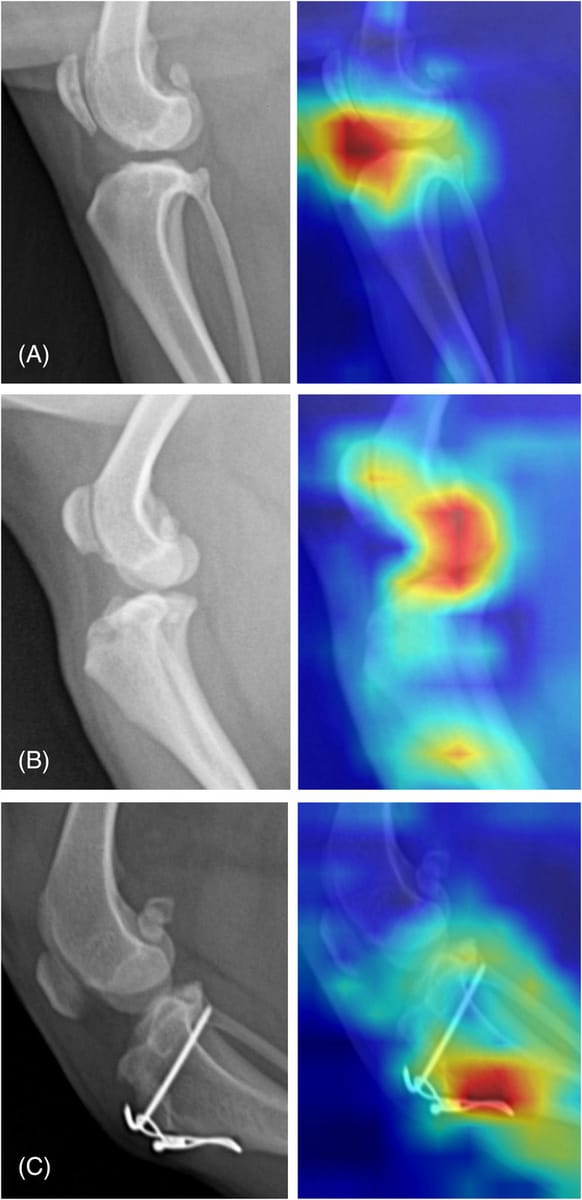

Comparison of the Gradient-weighted Class Activation Mapping for the joint effusion classification model. A, Correctly localized example. B, poorly localized example. C, image with implant. If the model accurately localized the radiographic findings, the infrapatellar fat pad region is marked in red. Otherwise, if the model poorly was localized, the color map is seen in the distributions. Gradient-weighted Class Activation Mapping for images with implants show that the CNN model paid the strongest attention to the implant.